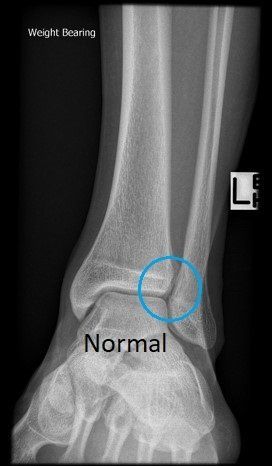

Weight-bearing X-rays comparing both ankles are useful, with MRI, weight-bearing CT and even ankle arthroscopy sometimes required to determine whether the syndesmosis is stable or unstable (see images below).